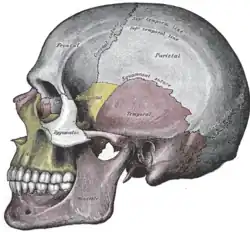

Osso zigomático esquerdo. Superfície temporal. Visão lateral do crânio.

Visão lateral do crânio. Fossa infratemporal esquerda.